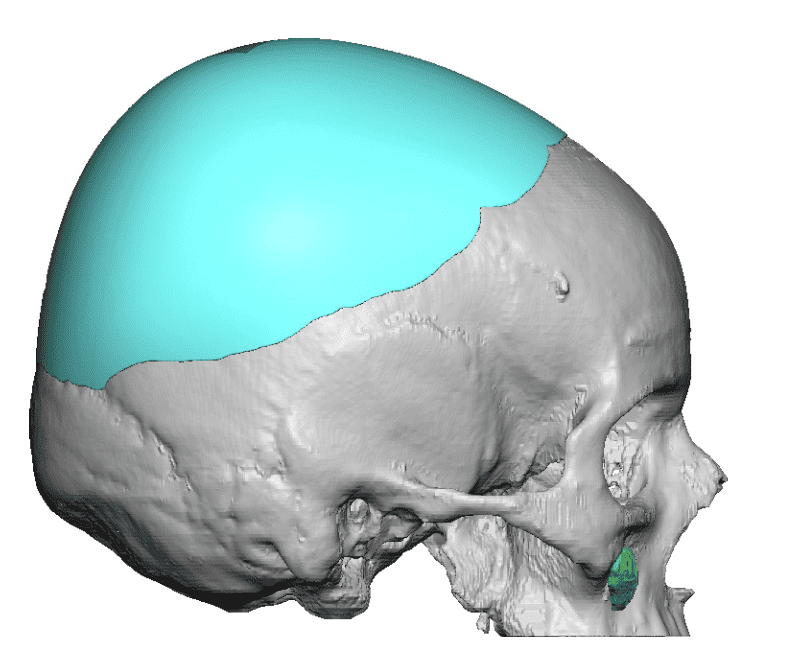

Patient 110

Desire for head shape asymmetry improvement as the final stage of total skull reshaping surgeries. (previous skull implants are in green color)

Placement of custom temporal implant through an incision behind the ear.

Desire for head shape asymmetry improvement as the final stage of total skull reshaping surgeries. (previous skull implants are in green color)

Placement of custom temporal implant through an incision behind the ear.